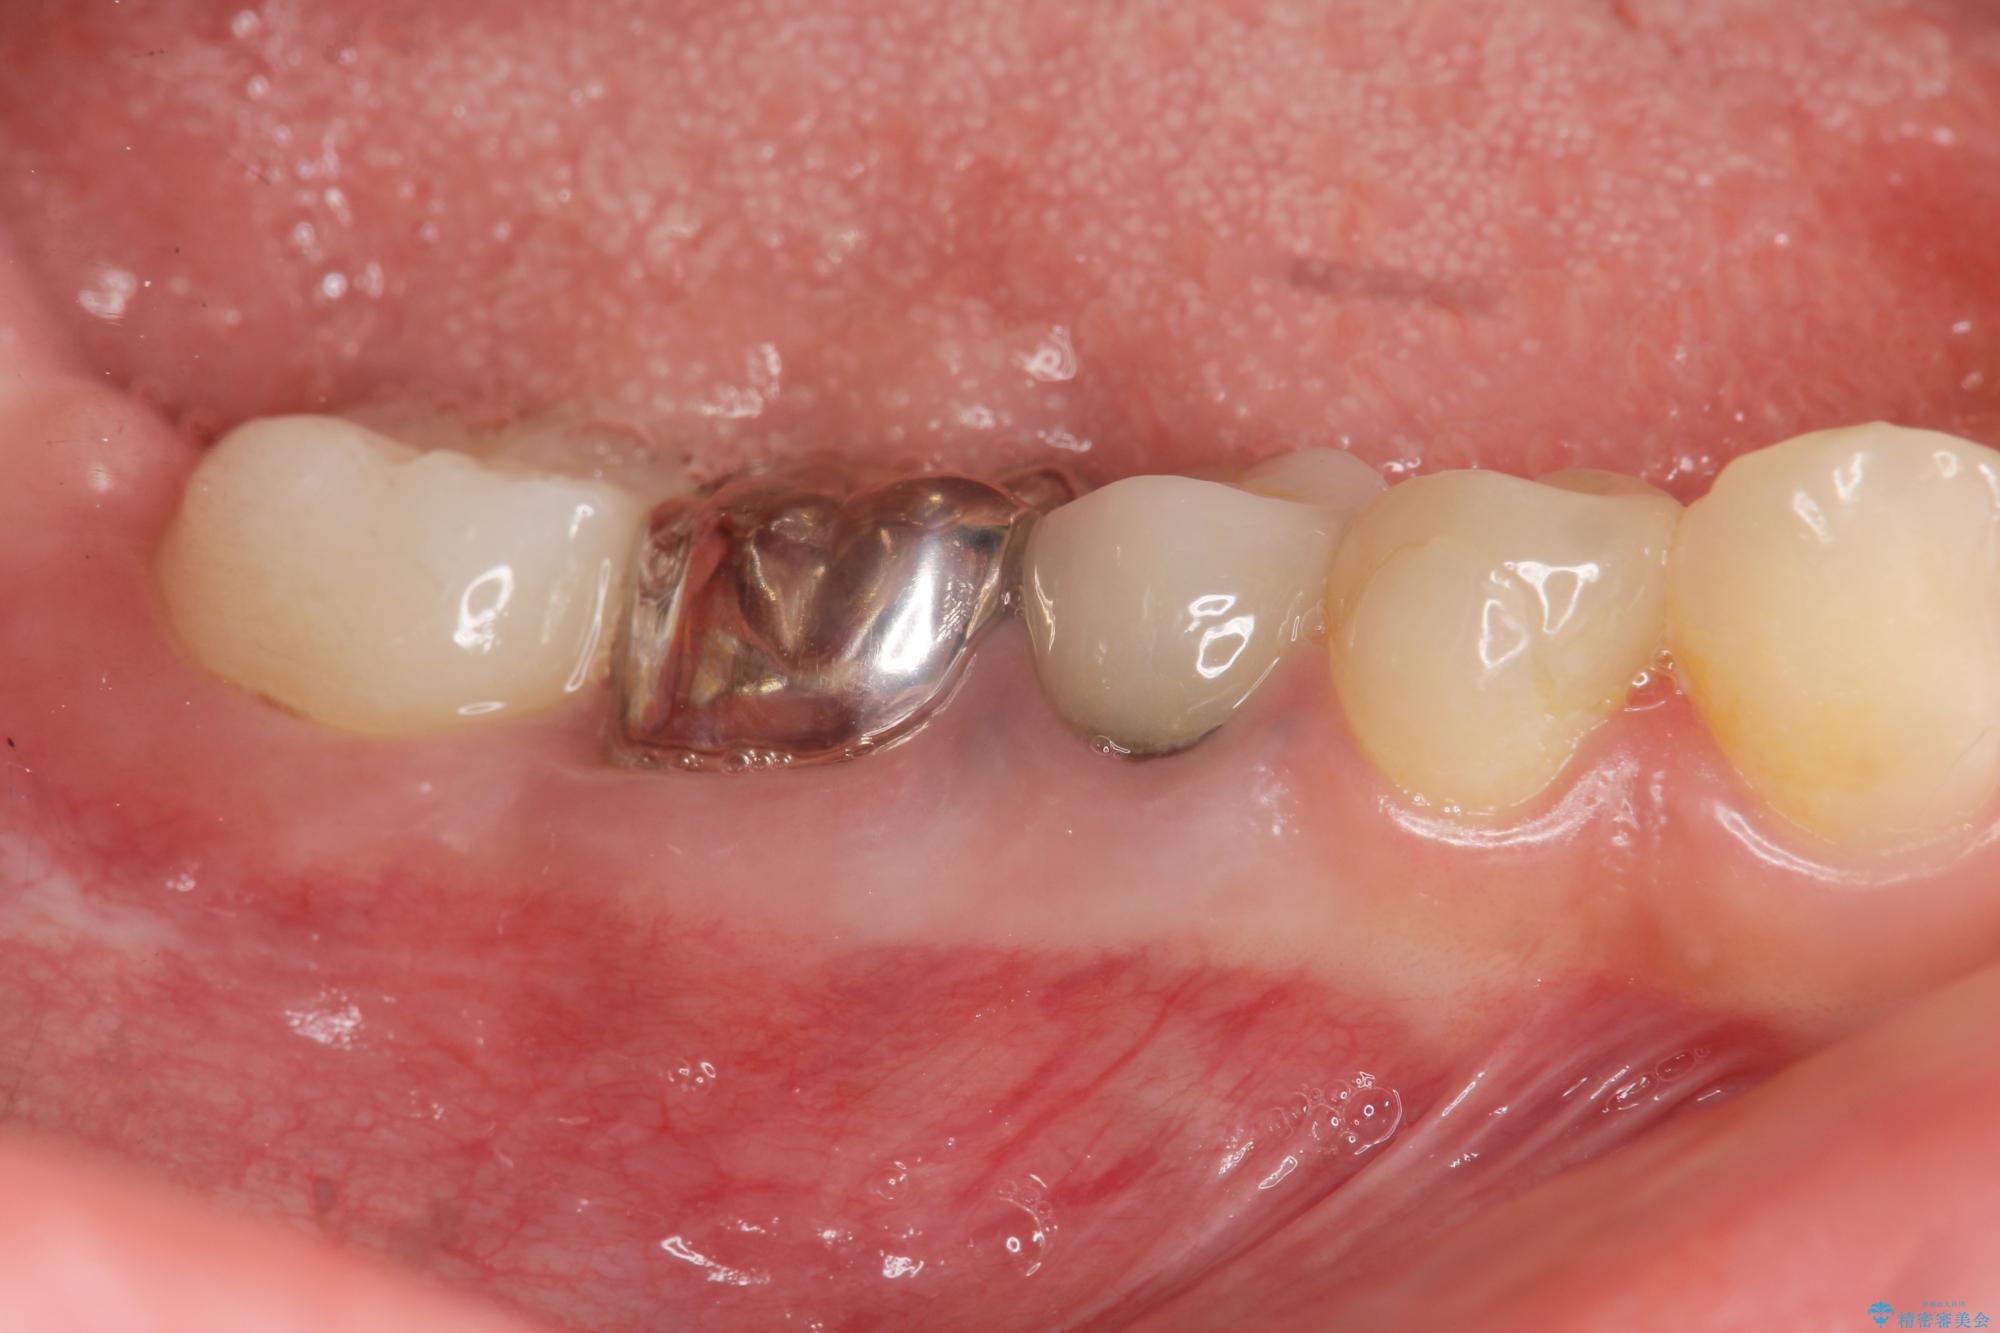

治療中

遊離歯肉移植術を伴うインプラント治療 治療中画像 遊離歯肉移植術を伴うインプラント治療 治療中画像 遊離歯肉移植術を伴うインプラント治療 治療中画像 遊離歯肉移植術を伴うインプラント治療 治療中画像 遊離歯肉移植術を伴うインプラント治療 治療中画像 遊離歯肉移植術を伴うインプラント治療 治療中画像